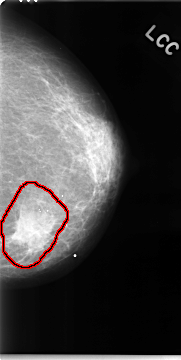

FILE: C_0050_1.LEFT_CC.OVERLAY

TOTAL_ABNORMALITIES 1

ABNORMALITY 1

LESION_TYPE MASS SHAPE IRREGULAR MARGINS SPICULATED

ASSESSMENT 5

SUBTLETY 5

PATHOLOGY MALIGNANT

TOTAL_OUTLINES 1

BOUNDARY